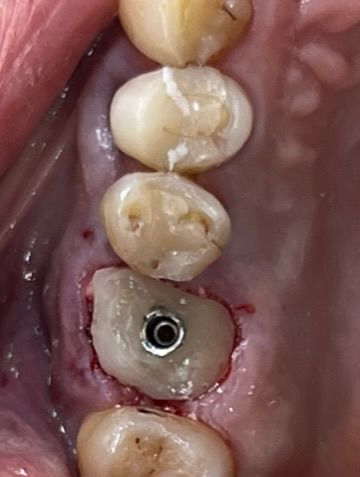

6. Immediate implant placement Ø 6.4mm Axiom® X3, 4 mm deep from the gum margin in the bone furcation for mucointegration.

6